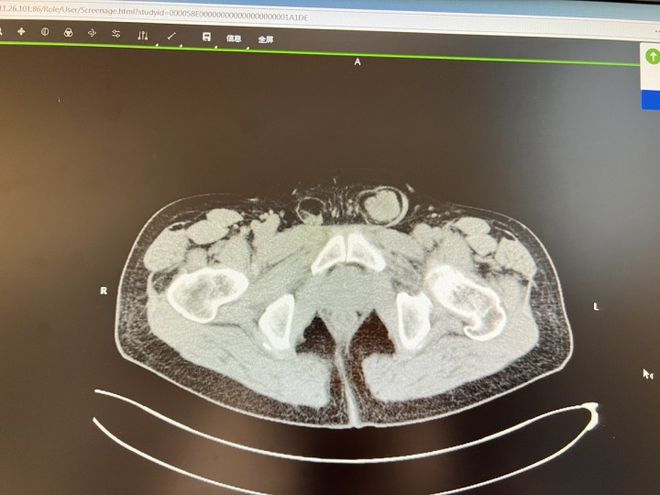

哎呀,说到这个股疝手术啊,真是让我又紧张又兴奋!首先得知道,股疝可不是闹着玩的,它是指肠子或其他组织通过股环突出到腹股沟下面,那感觉,真是让人坐立不安。

手术开始前,医生会给患者来个全身麻醉,确保在手术过程中不会感到任何疼痛。接着,医生会在腹股沟区画个小圈,这就是手术切口的位置啦。切口一开,医生就得小心翼翼地把那些突出的组织给推回去,这可不是件容易的事,得非常仔细,不能有丝毫马虎。

然后,医生会用一种叫做修补网的东西来加固那个薄弱的股环,这网就像是我们平时用的补丁,贴上去就能让那个地方变得结实多了。最后,缝合切口,贴上敷料,手术就算大功告成了。